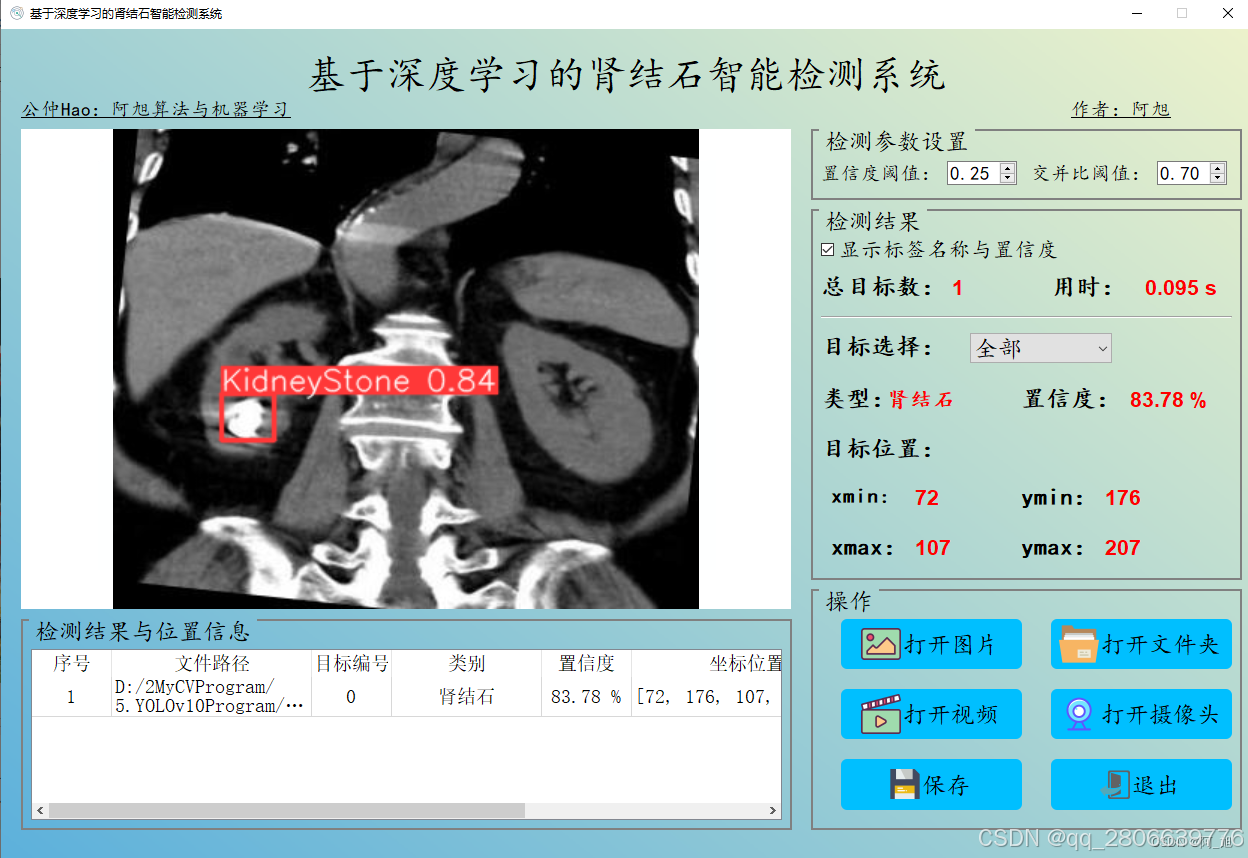

CT扫描图像的肾结石智能检测系统在医疗诊断方面提供了一种快速、准确的辅助工具,显著提高了医生识别和评估肾结石的效率。本文基于YOLOv10深度学习框架,通过1300张CT扫描的肾结石相关图片,训练了一个进行肾结石目标检测的模型,可以对CT扫描图像中的肾结石进行实时检测。并基于此模型开发了一款带UI界面的肾结石智能检测系统,更便于进行功能的展示。该系统是基于python与PyQT5开发的,支持图片、视频以及摄像头进行目标检测,并保存检测结果。本文提供了完整的Python代码和使用教程,给感兴趣的小伙伴参考学习,完整的代码资源文件获取方式见文末。

部分截图如下: